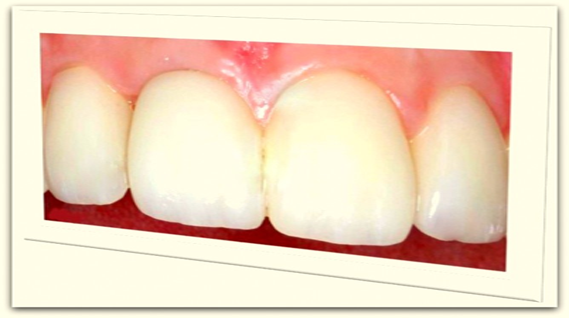

“The QDC Dental Implants”

look and feel like your very natural teeth designed to be fixed for lifetime.